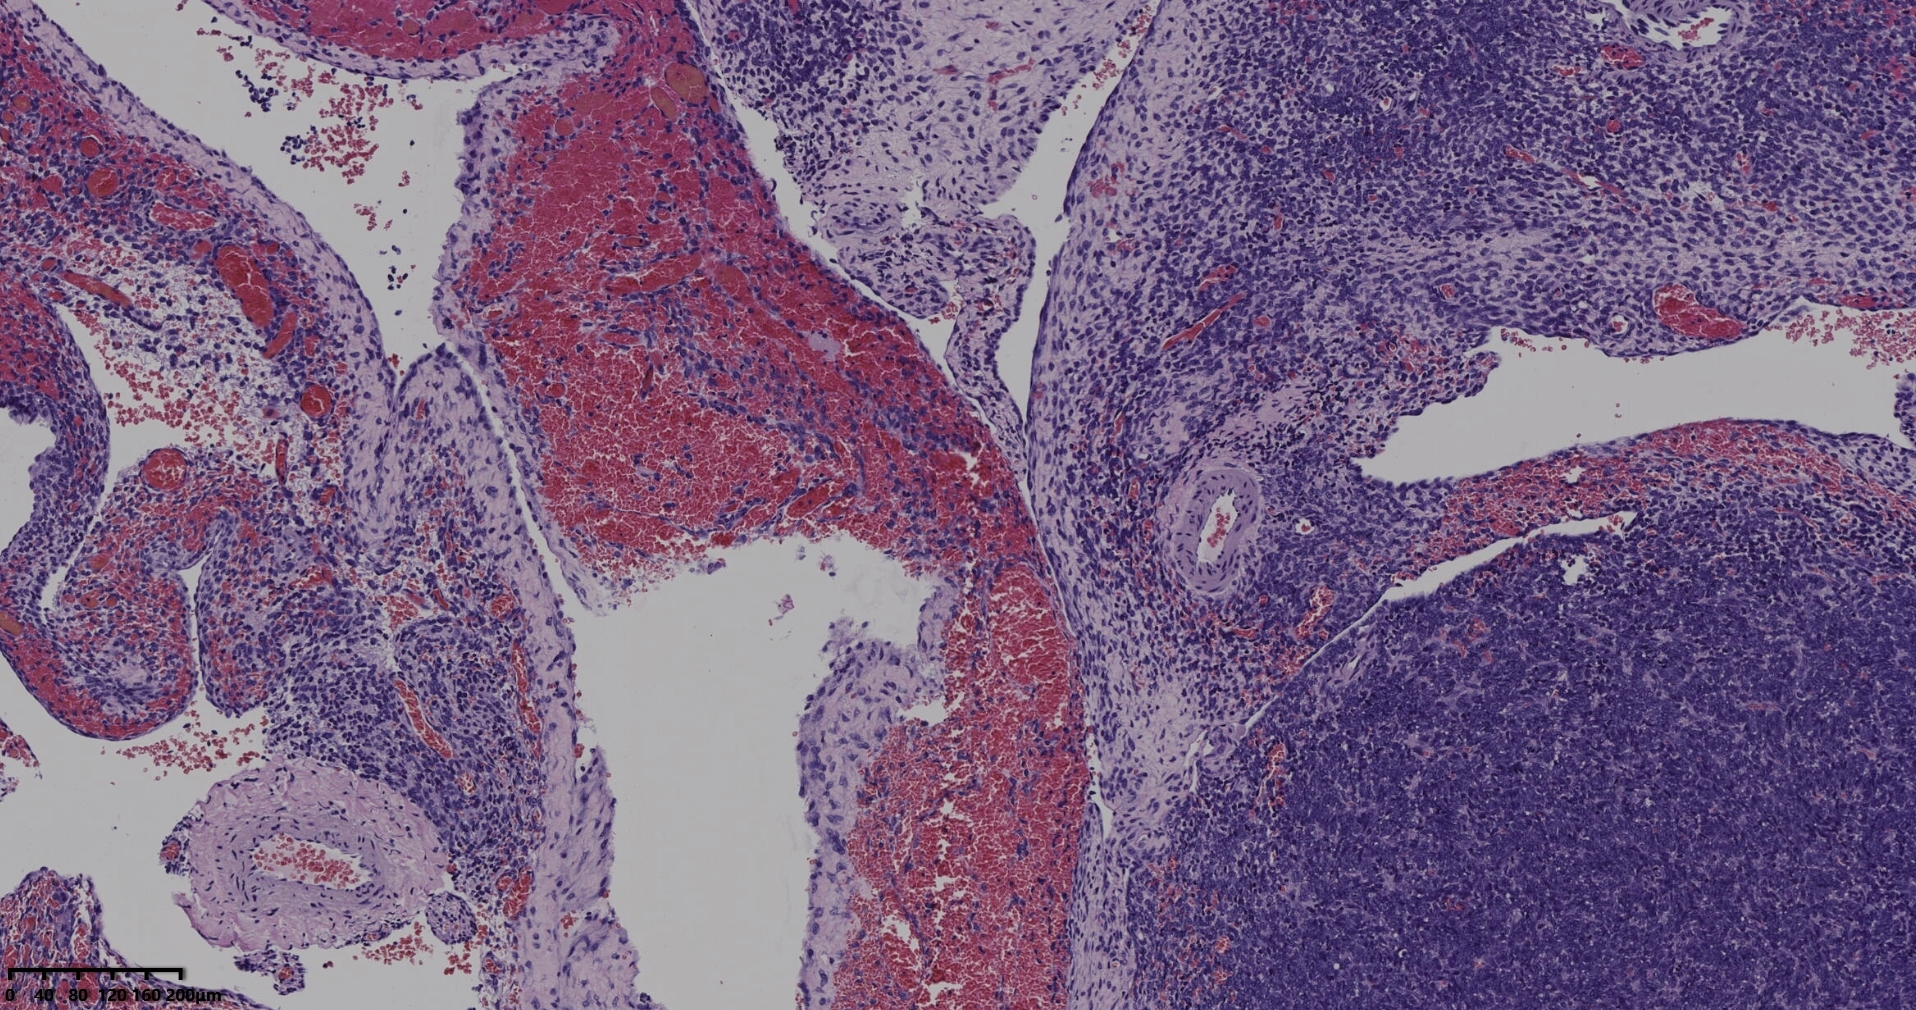

彩超提示盆腔肿物,不规则囊实性肿物,囊性有间隔,其中可见略高密度影,体积约18*10*7厘米

葡萄状多囊状肿物1个,体积约15*10*8厘米,囊壁后约0.1厘米,光滑,囊内可见灰黄粘液,囊肿之间可见实性区,体积约8*5*5厘米,切面黄色,实性,质地脆。

冰冻切片取两块实性区组织,其中1块可见梭形细胞为主,另一块似上皮样细胞,细胞丰富密集。

常规切片

考虑颗粒细胞瘤。